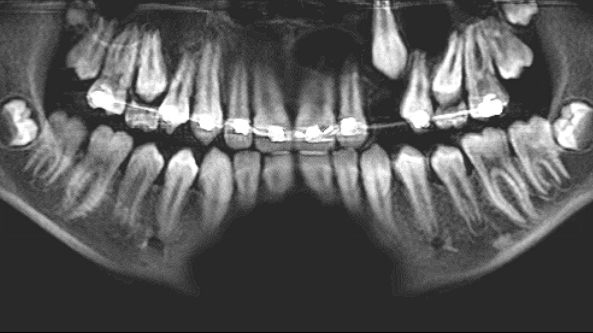

At the time of publication, the lesion described had reduced in size dramatically, now extending from tooth nos. 10–12. The floor of the maxillary sinus ossified as well. The time elapsed since the marsupialization procedure was six months. Removal of the residual cyst with immediate bone grafting would be performed shortly, likely including the sacrifice of the lateral incisor and second bicuspid. Although this is a large defect, it will be much more easily managed than that posed if marsupialization had not been utilized (figure 7).